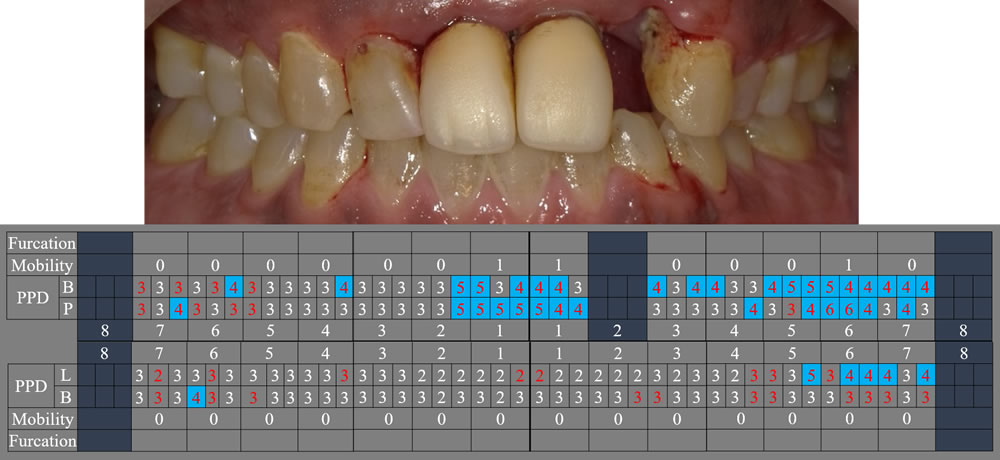

【初診時の口腔内】

患者様に話を聞くと、今までに虫歯治療で歯を削った記憶はほとんどないとのことでした。確かに、前歯以外は虫歯治療の痕跡がありません。しかし、歯周病の検査をすると問題点が見えてきました。※写真でもお分かりいただけるように、歯周病検査時に歯ぐきからの出血が確認できました。

歯周病検査の表です。歯周ポケットの深さ正常値3㎜を超える(=歯周病の進行している)部位が口腔内全体に確認できました。赤色の部分は検査時に出血のあった個所です。上顎は多くの箇所で出血がありました。歯周病の症状改善には、専門的な歯周病治療に合わせて適切なセルフケアが必須です。患者様の協力なしでは決して治療は成功しません。